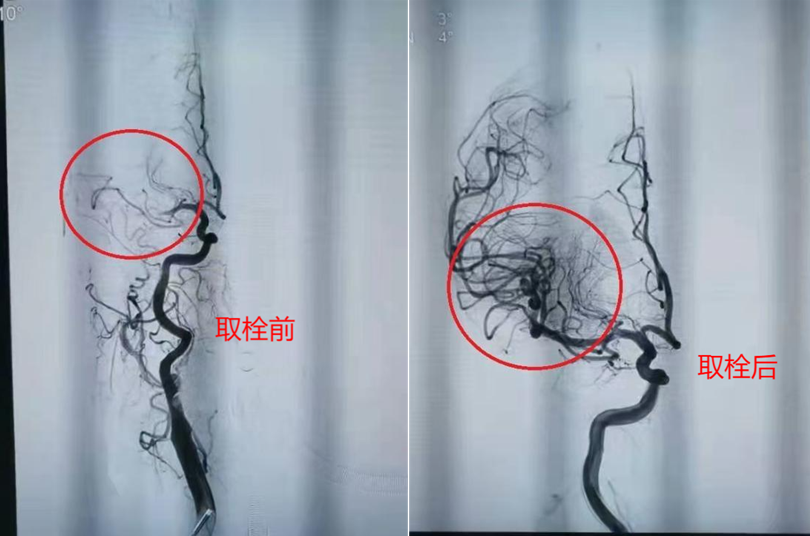

脑梗死动脉取栓术,简称为“取栓术”,是一种微创的血管内介入手术。它的核心目标是快速移除堵塞在颅内大动脉的血栓,重新开通血管,恢复大脑的血液供应,从而最大限度地拯救濒临死亡的脑组织。

(二) 动脉取栓术:直接作用于血栓本身,物理取栓,开通率高。与静脉溶栓相比动脉取栓的时间窗延长:对于符合条件的患者,时间窗可以延长至发病后6~24小时(需要通过影像学评估,筛选出仍有可挽救脑组织的患者)。对大血管闭塞效果显著:是大血管闭塞性脑梗死的首选治疗方案。